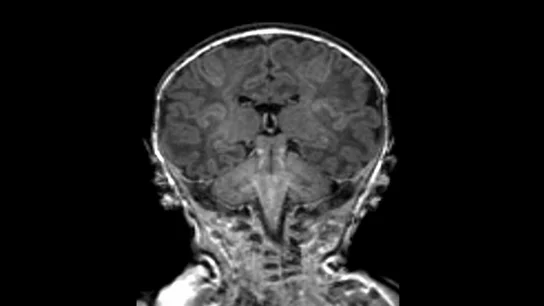

Natural también muestra cómo es el estudio pionero en el mundo en el que miden la contaminación y el desarrollo del feto durante el embarazo. Tras hablar con Mar Álvarez, coordinadora del proyecto BiSC, se llega a una conclusión: la contaminación del aire también afecta cerebro del feto de una mujer embarazada.